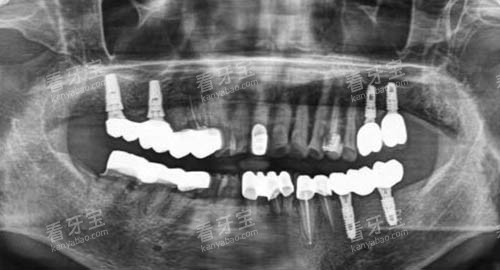

在进行种植牙手术前,医生会对患者的口腔情况进行超全、细致的检查,包括口腔X光片、CT扫描等,比较准了解患者的牙槽骨条件、牙齿缺失情况等。